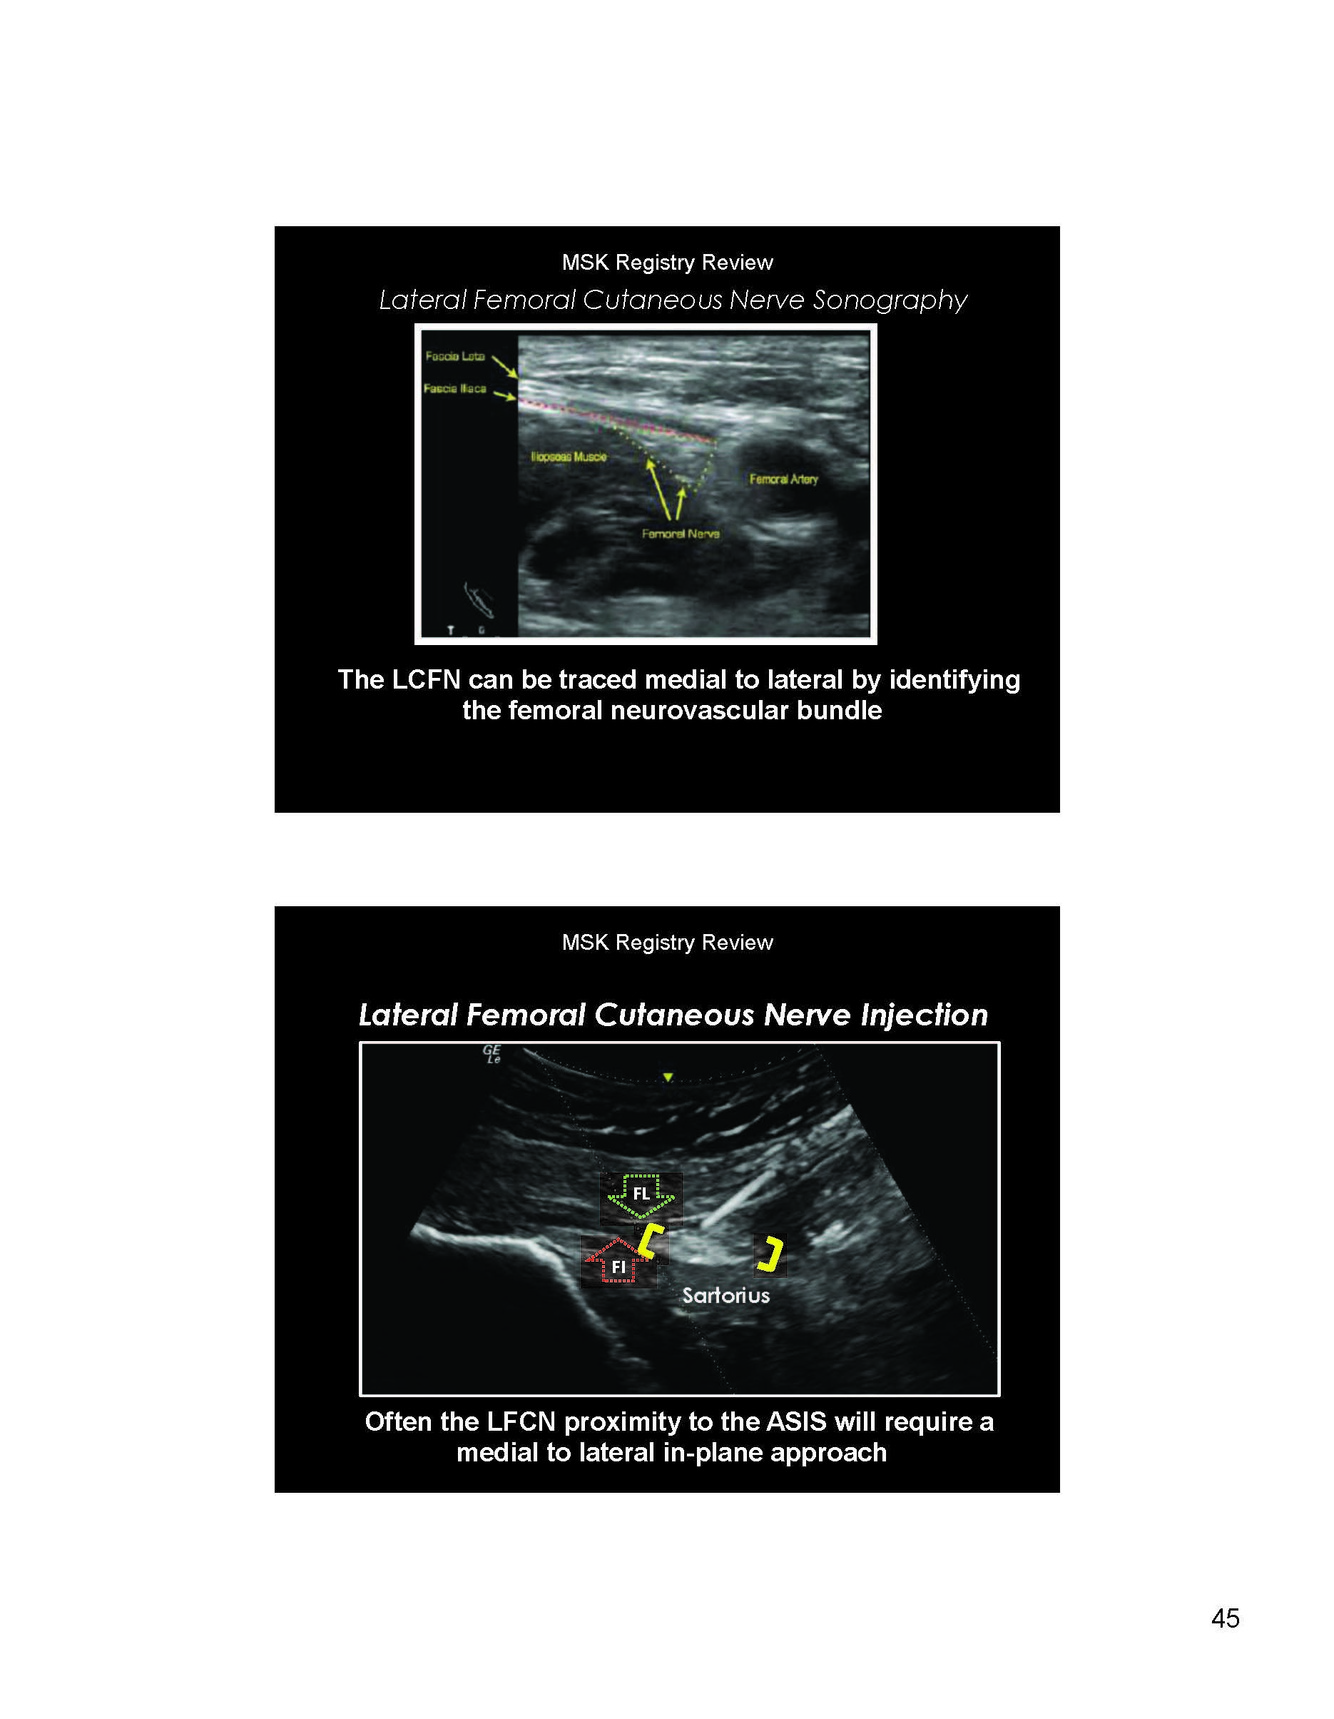

Where do you place the probe to view the conjoined hamstring?

LAX inferior and medial

Where do you place the probe to image the semimembranosus

LAX superior and lateral